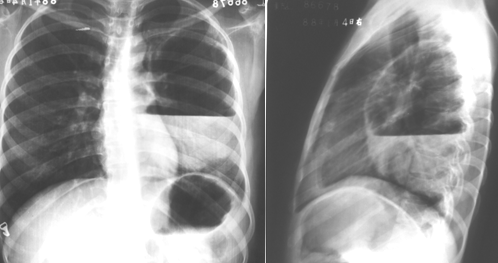

左下叶支气管扩张

图片

左下叶支气管囊状、柱状扩张

右肺支气管扩张

右肺支气管呈囊状、柱状扩张